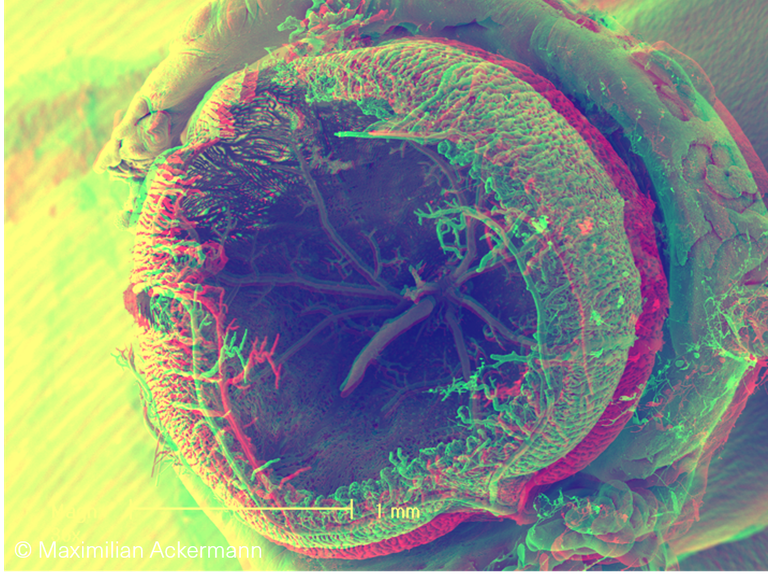

Ocular vascular plexus

Anaglyphic 3D SEM image of microvascular corrosion cast  demonstrates the microvascular hierarchy in the mature murine eyeball.